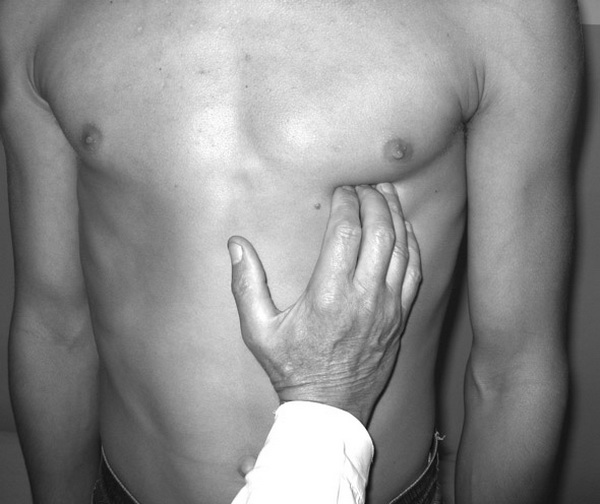

Рис.1. Положение больного с хронической сердечной недостаточностью.